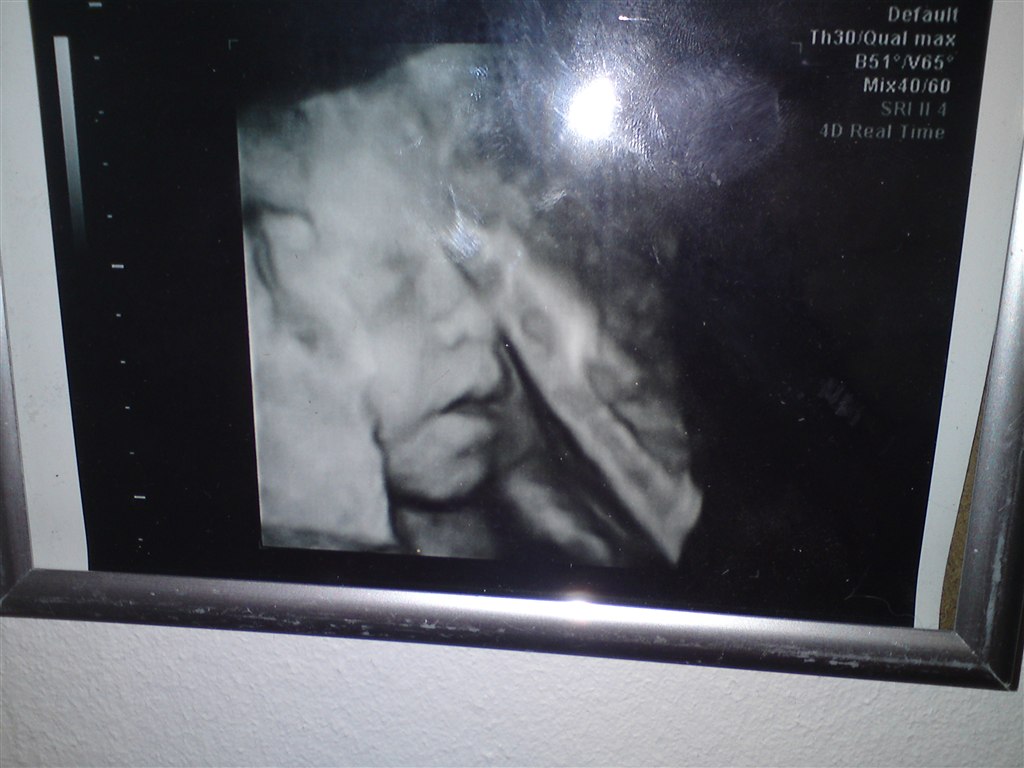

Her er et fra min 3d/4d scanning

Hvor ser det vildt ud